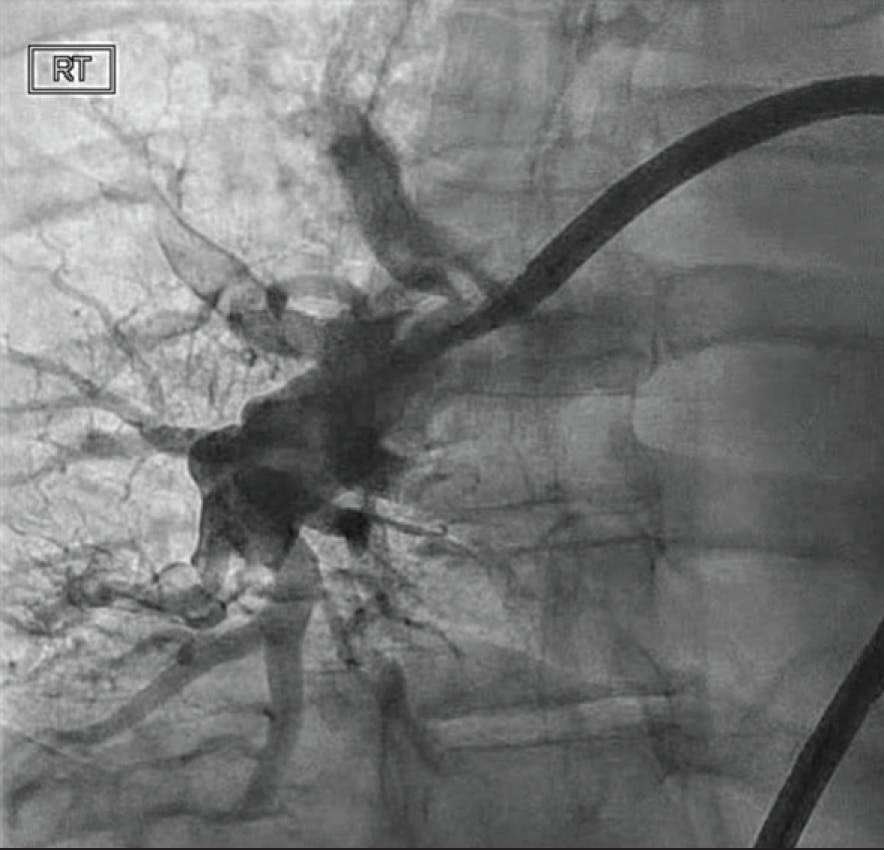

The patient was placed supine on the angiographic table with bilateral groins prepped and draped in sterile fashion. Access was obtained in the right common femoral vein utilizing real-time ultrasound and fluoroscopic guidance with a micropuncture kit with subsequent placement of a 7-F sheath. Over an Amplatz Super Stiff 0.035-inch guidewire (Boston Scientific Corporation), the venotomy was dilated and a 16-F Gore DrySeal sheath (Gore & Associates) was inserted. A 7-F balloon-tipped PA catheter was advanced under fluoroscopic guidance into the right atrium, right ventricle (RV), and left PA, at which time pressures were obtained and cardiac output/index was calculated. Pulmonary angiography of the left PA was performed under digital subtraction angiography, demonstrating large central thrombus occluding the left upper lobe and near occlusive in the left lower lobe.

Figure 1. Preprocedural angiogram of the left PA.